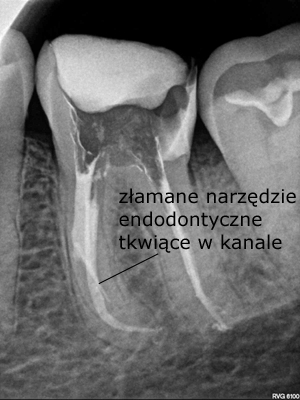

27-latni pacjent zgłosił się do naszej placówki z prośbą o pomoc polegającą na kontynuacji leczenia kanałowego, trwającego już wiele miesięcy. Leczenie przedłużało się z powodu powikłania w postaci złamanego narzędzia endodontycznego, które uniemożliwiało dezynfekcję systemu kanałowego na całej długości. Dodatkową trudnością była lokalizacja narzędzia w połowie długości korzenia za krzywizną kanału, co uniemożliwiało jego widoczność w mikroskopie. Podjęto próbę ominięcia („by passa”) narzędzia, co niestety nie powiodło się. Nieocenioną pomocą w tym precyzyjnym zabiegu okazała się tomografia wolumetryczna, która „sięgała, gdzie wzrok nie sięgał” i ułatwiła bezpieczne usunięcie narzędzia, a następnie pełną dezynfekcję i szczelne wypełnienie systemu korzeniowego. Zabieg trwał 4 godziny (2 wizyty po 2 godziny) i dzięki olbrzymiej cierpliwości pacjenta i precyzji operatora zakończył się sukcesem.